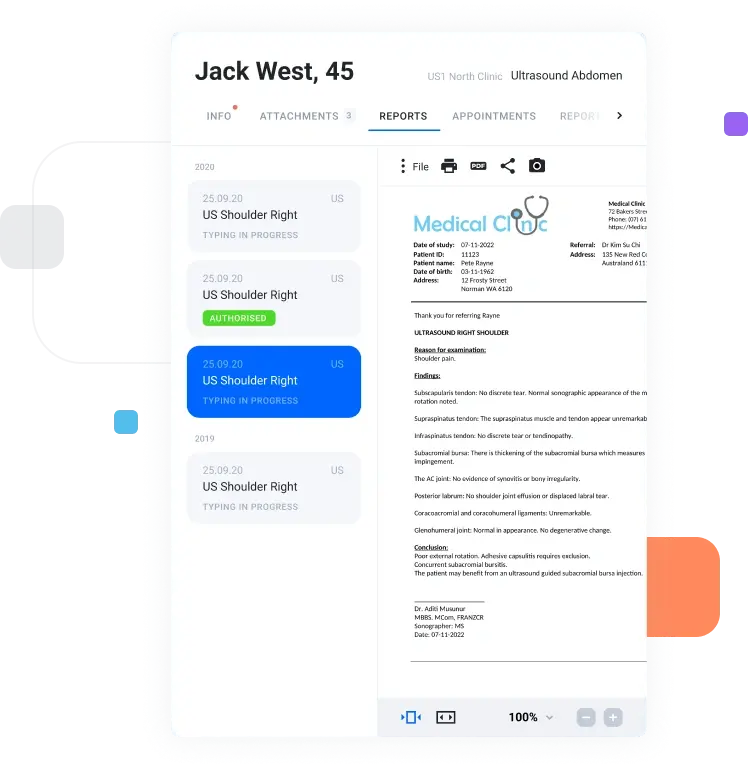

Open studies instantly

with a zero-footprint

viewer

Give radiologists and referrers browser-based access to current studies and priors without installing heavy desktop software at every location.